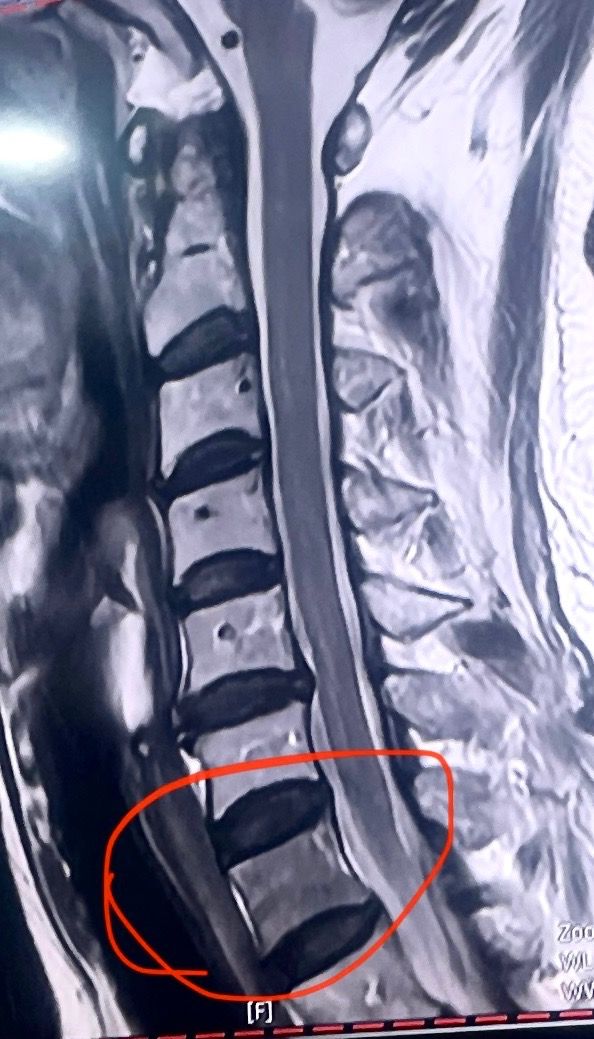

경추 mri 시 뼈가 어둡게(까맣게) 보이는 곳

안녕하세요. 65세 부모님, 몸이 아프고 손발이 저릿하여 mri 를

찍었는데 목 뼈 동그랗게 체크 된 부분이

어두워(까맣게보여) 골수암 의심 판독을 받았습니다. 조형제를 넣고 검사를 다시 해야 한다고 하는데, 사진상으로 봤을때 문제가 있을지 문의 드립니다. 참고로 최근 피검사에서 따로 문제 되는 부분은 없었는데, 골수암일 경우에 백혈구, 적혈구 수치에 변화는 없을까요? 감사합니다

MRI에서 어둡게 보이는 병변이 반드시 골수암을 의미하지는 않습니다. 양성 변화도 가능하며,말씀하신대로 조영제로 추가 검사가 필요합니다.

골수암이 있을 때는 백혈구, 적혈구, 혈소판 수치가 흔히 변하지만, 초기나 국소 병변에서는 혈액검사가 정상일 수 있습니다.

조영증강 MRI 등 추가 검사를 통해 정확한 진단을 받으시기 바랍니다.